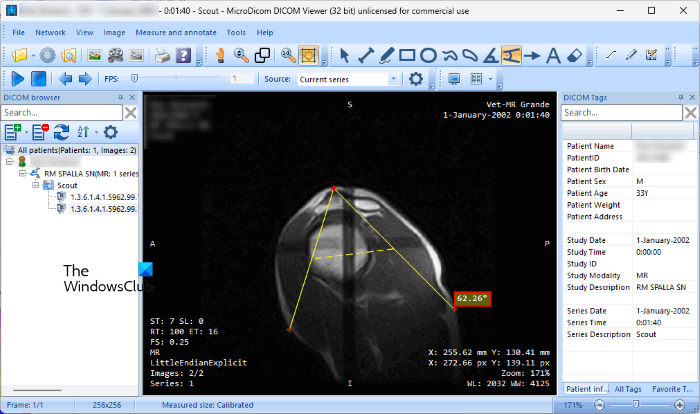

1] MicroDicom

MicroDicom is free for non-commercial use. If you are a medical student, you can use it for free. When you run it for the first time, it will ask you to register MicroDicom. Select the desired option. You can open either a DICOM image or select a folder containing the DICOM images.

After opening a DICOM image, you can measure and annotate it. All the tools to annotate the DICOM image are available on the Toolbar or you can click on the Measure and Annotate menu for the same. You can measure the distance and angle between two points on the image and also calculate the Cobb angle.

Apart from the measurement, you can also annotate the DICOM images by inserting text, drawing shapes and curves, drawing free-hand drawings, etc. You can view the patient information and DICOM tags on the right side. You can also apply different presets to the DICOM image, like full dynamic, skull, lung, spine, bone, etc.

It also lets you export the DICOM images in different image formats, including BMP, PNG, JPG, etc. Apart from that, exporting a DICOM image to a video file, DICOM file, text file, and clipboard are also available.

To download MicroDicom, visit its official website, microdicom.com.